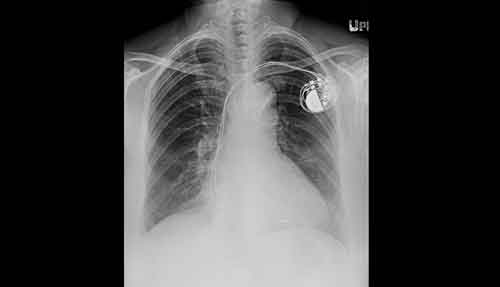

Pacemaker/implanterbar defibrillator. Om patienten har pacemaker/implanterbar defibrillator rekommenderas minst 8 cm avstånd mellan den implanterade dosan och de externa elektroderna samt anteroposterior elektrodplacering för att undvika skador på systemet [12]. Palpera därför dosans kanter för att säkerställa placeringen. Kontroll av funktionen av pacemaker/implanterbar defibrillator (avkänning, trösklar, impedans) efter elkonvertering är tillrådligt.

Ett avstånd på minst 8 cm rekommenderas mellan eventuell implanterad dosa (pacemaker/intern defibrillator) och de externa elektroderna. Dosans kanter bör palperas för att säkra placeringen.